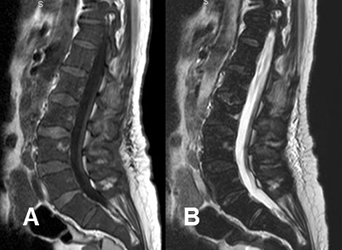

Fig 13 B. Leucemia.

A: RM sagital en T1 y B: RM sagital en T2. Hipointensidad de la medula ósea en T y T2, por Infiltración leucémica. La señal es baja en T2, por la alta celularidad.